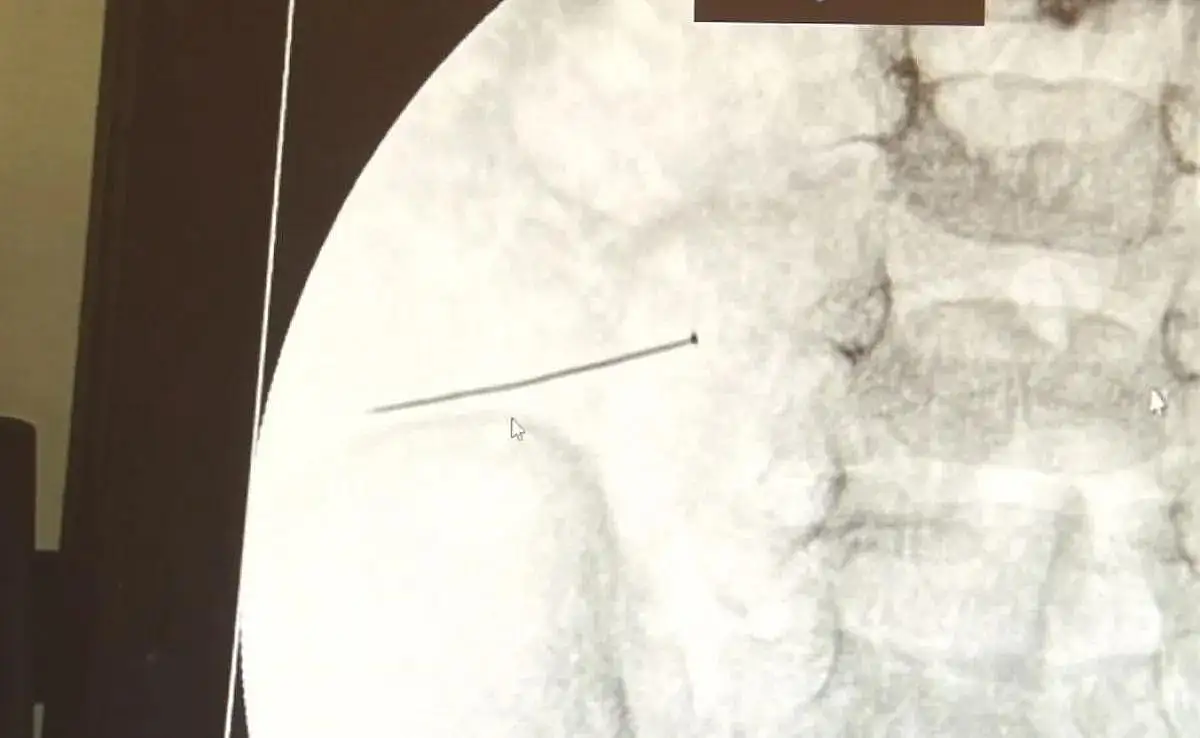

Burada yapılan tetkiklerde 2 yaşındaki çocuğun ince bağırsağında yaklaşık 3 santimlik toplu iğne olduğu ve bağırsağı deldiği belirlendi.

Ertesi gün bağırsakta delinmeyle sonuçlanmış ve çocukta da ciddi semptomlar meydana getirmişti. Bu şekilde hasta bize başvurdu. Tetkikler sonucunda yabancı cismi tespit ettik, semptomları ve bulgularına göre de çocuğu ameliyata aldık. Yaklaşık 3 santim boyunda bir toplu iğnenin ince bağırsağı deldiğini, ince bağırsaktaki içeriğin de karın içerisine dolduğunu gördük. Ameliyatı başarılı bir şekilde tamamladık, yaklaşık 1 saat süren bir ameliyattı"

Öte yandan, yaklaşık 3 santimlik toplu iğne filme yansıyan görüntüsüyle gözler önüne serildi.